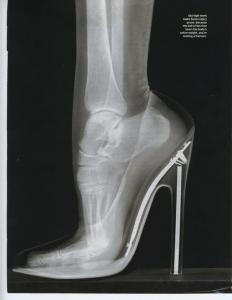

yozz Posted April 14, 2012 Posted April 14, 2012 If you magnify the picture a few times you can read: Sky high heels make bones injury prone. Because the ball of the foot bears the body's entire weight, you're inviting a fracture. Y. Raise your voice. Put on some heels.

yozz Posted April 14, 2012 Posted April 14, 2012 I am not understanding all of it. If you have the habit to walk on the front part of your feet, or walk on tiptoe, you are also placing all your weight on the ball of your foot. I do not think that endangers your foot. I have been walking like that the whole of my life and never had any problems. I think that there are many people who believe that if you do not do like them, you must be doing something wrong. Most likely it involves you being stupid or something even more horrible. Cf men wearing heels! Gasp! Y. Raise your voice. Put on some heels.